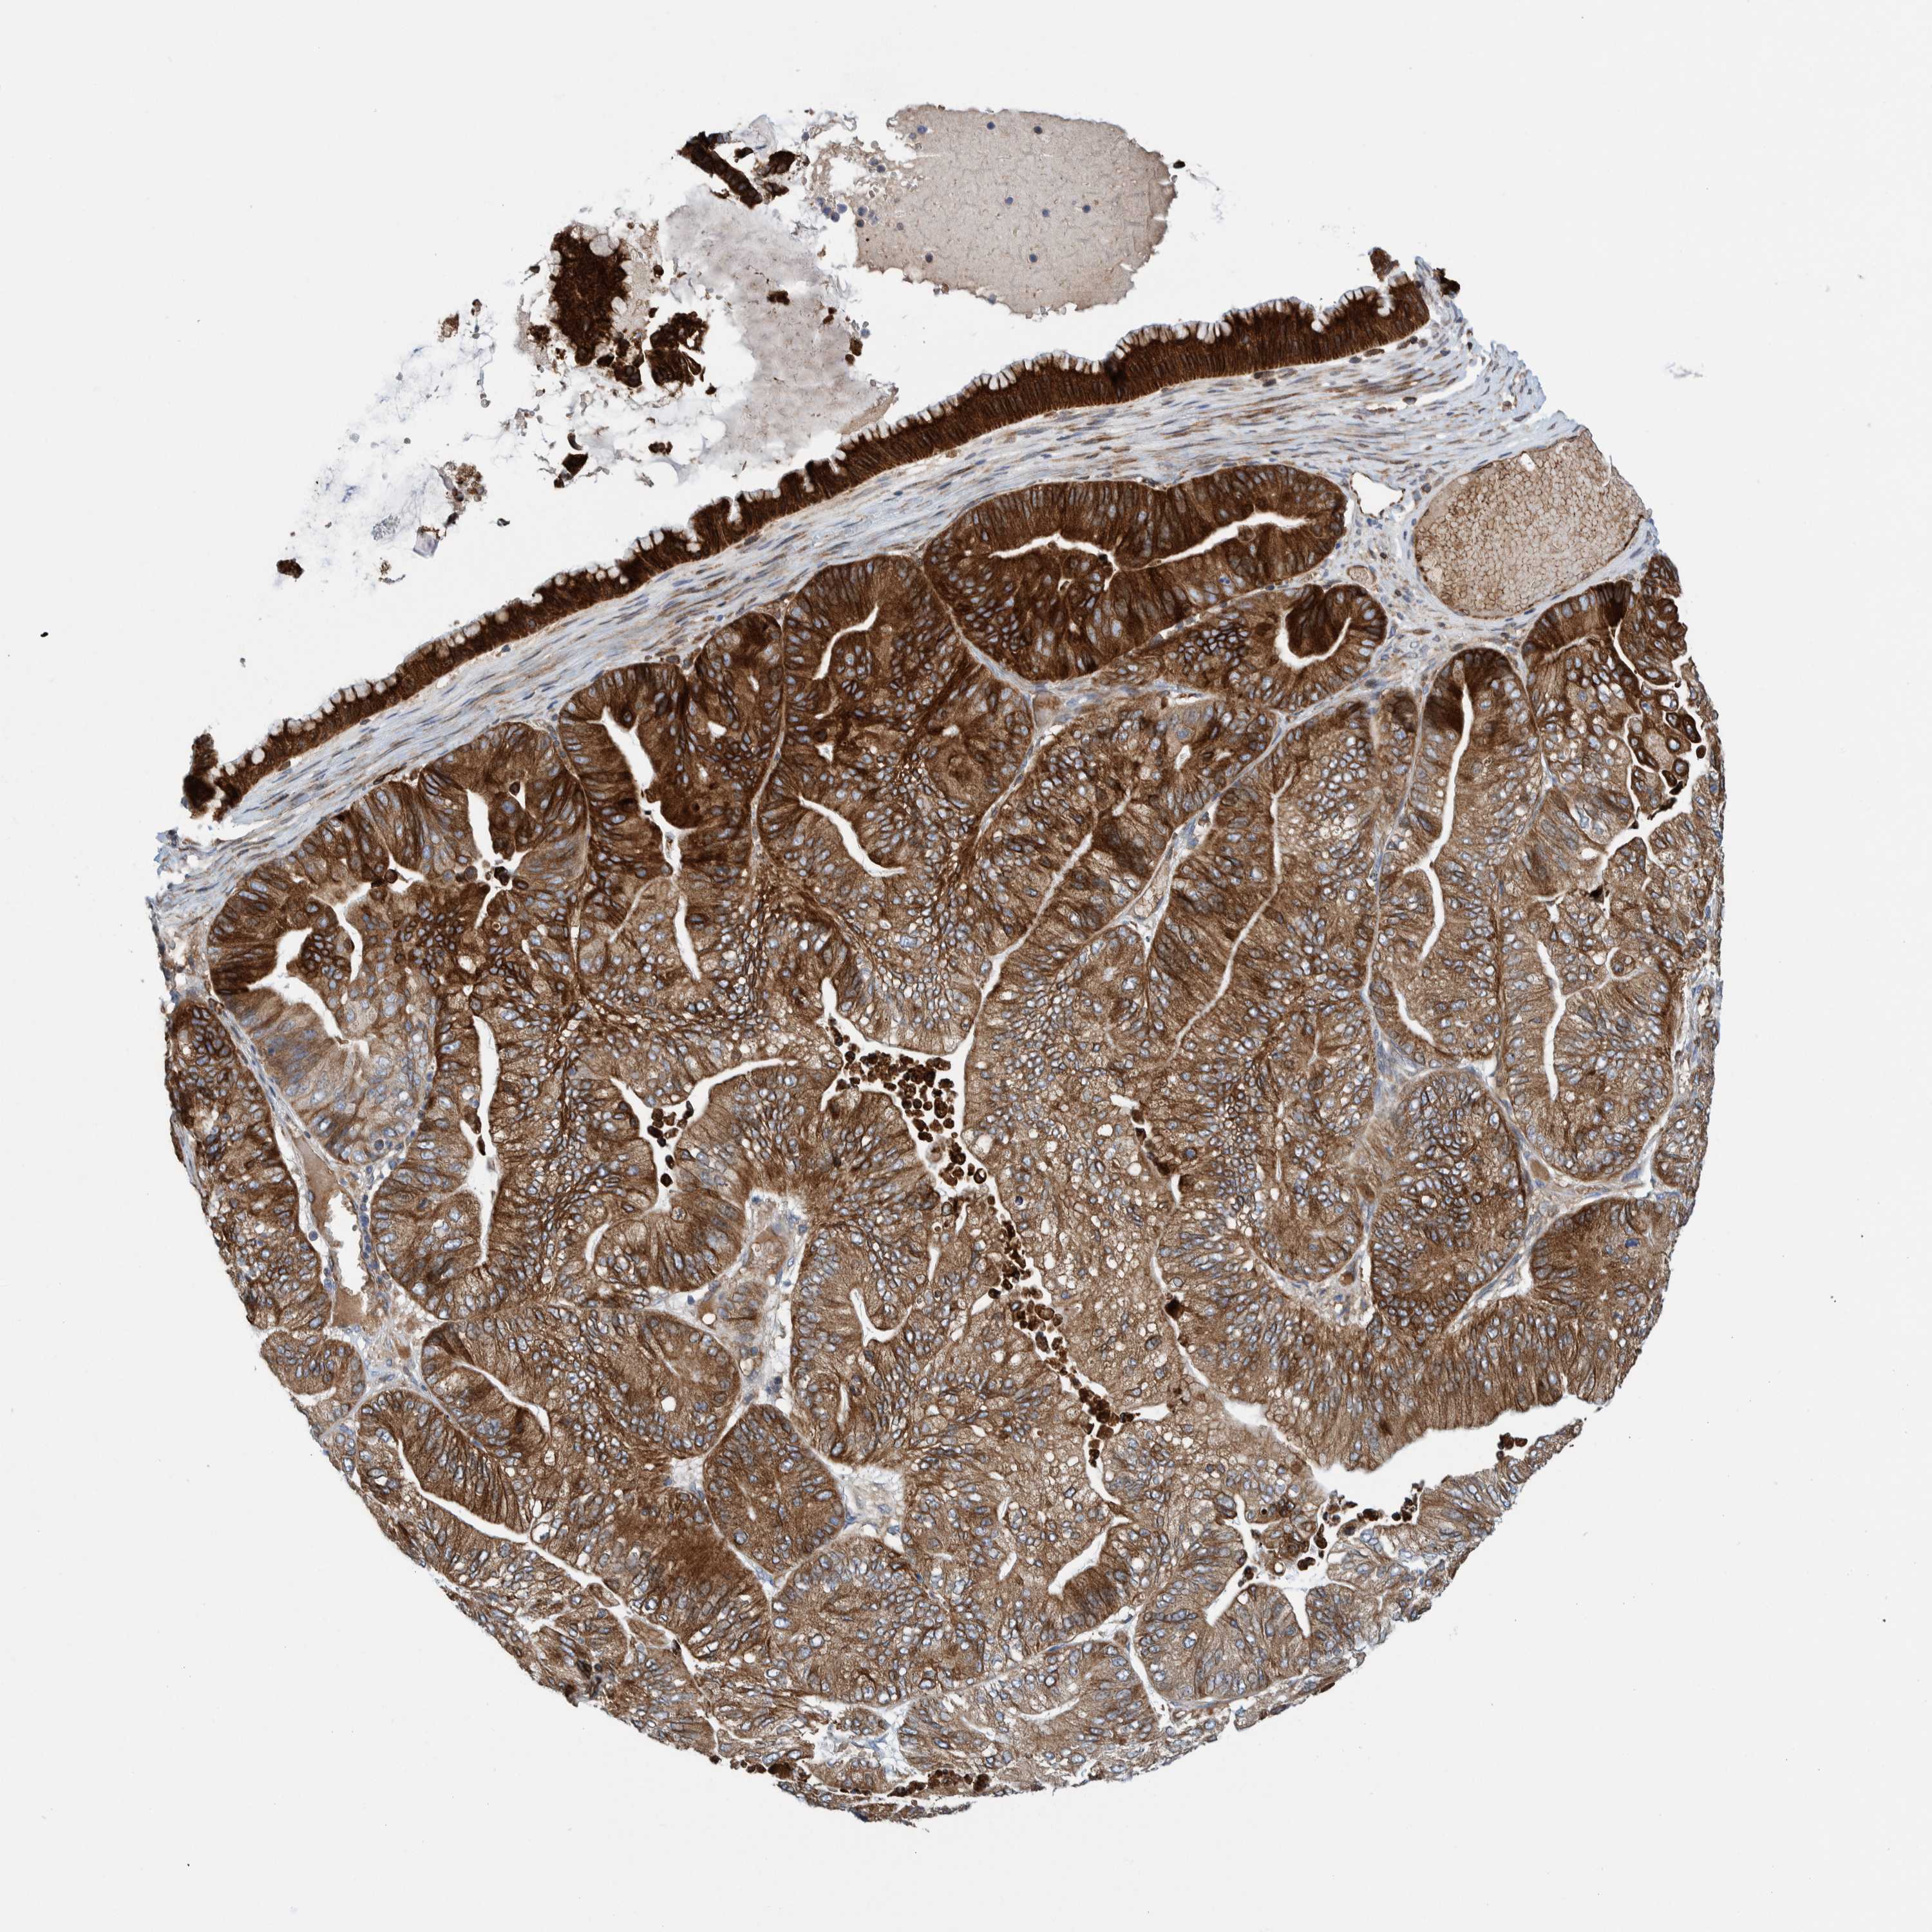

OVARIAN CANCER - Protein expressioni

A mouse-over function shows sample information and annotation data. Click on an image to view it in a full screen mode. Samples can be filtered based on level of antibody staining by selecting one or several of the following categories: high, medium, low and not detected. The assay and annotation is described here.

Note that samples used for immunohistochemistry by the Human Protein Atlas do not correspond to samples in the TCGA dataset.

Antibody stainingi

Antibody staining in the annotated cell types in the current human tissue is reported as not detected, low, medium, or high, based on conventional immunohistochemistry profiling in selected tissues. This score is based on the combination of the staining intensity and fraction of stained cells.

Each image is clickable and will lead to virtual microscopy that enables deeper exploration of all samples and also displays staining intensity scores, fraction scores and subcellular localization as well as patient and tissue information for each sample.

Antibody HPA023255

Staining

High

Medium

Low

Not detected

Intensity

Strong

Moderate

Weak

Negative

Quantity

>75%

75%-25%

<25%

None

Location

Nuclear

Cytoplasmic/membranous

Cytoplasmic/membranous,nuclear

Cystadenocarcinoma, serous, NOS

Carcinoma, endometroid

Cystadenocarcinoma, mucinous, NOS

Carcinoma, NOS